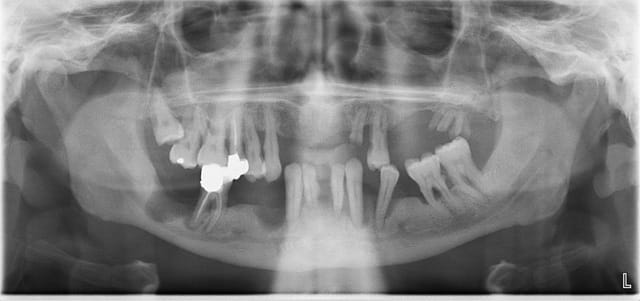

Ci-joint la pano d'un patient, 45 ans, bonne santé, fumeur, qui consulte suite à une bagarre et un choc frontal, bref, état de délabrement important comme vous pouvez le voir, j'ai deja extrait quelques restes radiculaires et dents mobiles,

Cependant je me pose des questions sur les grosses lacunes osseuses surtout en secteur 4, non douloureux, les dents de se secteur ont été extraites depuis de nombreuses années.. Je me pose des questions sur la conduite à tenir, j'ai monté un dossier pour l'adresser chez un stomato mais je ne trouve pas les causes de telles lacunes,

elles ont du être extraites pk grosse paro terminale cratérisée ces dents secteur 4. (si elles ont été extraites ... pas impossible qu'elles soient tombées d'elle même...)

Donc y avait déjà de gros trou avant les exos et l'os alvéolaire ne repousse pas dans ce cas ^^

ben le cratère en 44 était comme celui de 34. Mais çà c'était avant... lol